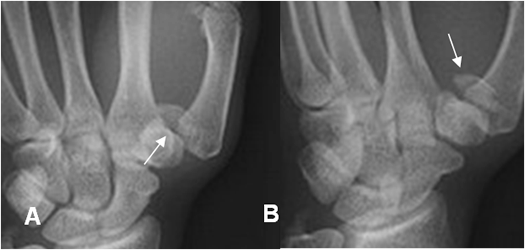

Fig 55. Fractura de los dedos.

A: Rx lateral. Fractura conminuta alrededor de la articulación interfalángica.

B: RX AP. Fractura oblicua del tercio distal de la falange media del 3º dedo.

C: Rx AP. Fracturas no desplazada en las bases de las falanges proximales de 2º y 3º dedo.